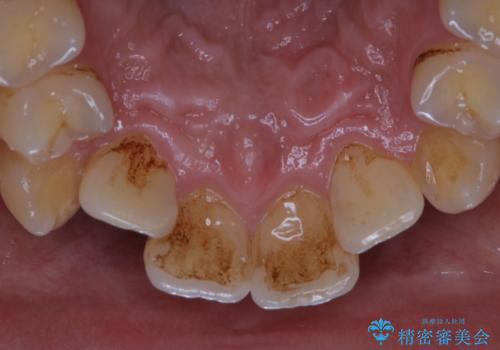

タバコのヤニをPMTCできれいに

- タバコによる着色が気になるため、全て取りたいとのことで来院されました。PMTC60分コースを行いました。

タバコに含まれているものの中で、タールというものが歯の着色の原因です。その、タールによって付着してしまった着色はご自身で落とすことはできません。